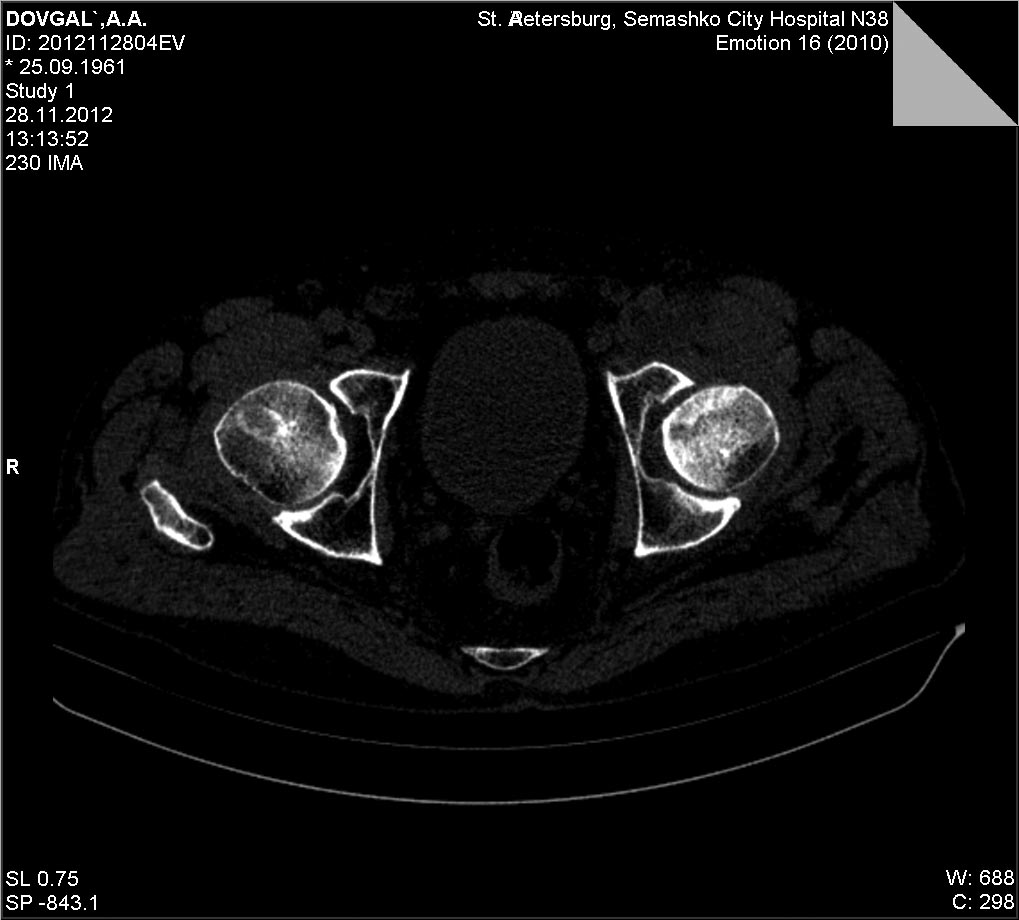

Доброго времени суток. Предлагаю к обсуждению случай с пациентом 51 года с переломом в передне-верхней зоне головки бедренной кости. С2.2 Мужчина, 51, направлен из травмпункта в наше ЛПУ с диагнозом " ушиб левого тазобедренного сустава". Со слов пострадавшего - 2 недели до поступления поскользнулся,упал с упором на левое колено. После чего появились боли в области левого тазобдренного сустава, боль при ходьбе, хромота, боль по передней поверхности тазобедренного сустава и в паху, боль усиливалась при осевой нагрузке, беспокоила в положении на спине, и на пострадавшем боку. Боль купировалась при сгибании в тазобедренном и коленном суставе в положении на спине. На стандартных рентгенограммах тазобедренного сустава патологии не выявлено.Госпитализирован в отделение с подозоением на импрессионный перелом головки бедренной кости Выполена компьютерная томография левого тазобедренного сустава, выявлено повреждение головки бедренной кости со вдавлением по передне-верхеней поверхности. На данный момент больному рекомендована разгрузка, ходьба без опоры на костылях до туалета, в остальном постельный режим. На обсуждение выносится ваш взгляд на дальнейшую тактику ведения больного, ваши наблюдения и предложения.В отделении мы рассматриваем следующие варианты: 1. Консервативное лечение с длительной разгрузкой, приемом хондропротекторов, сосудистых препаратов и т.д. 2. Возможность проведения ротационной остеотомии( есть небольшой опыт)

КТ

а был ли мальчик?сканы немного на разных уровнях, это просто место прикрепления связки, да и представить механизм такого перелома сложно, теоретически при заднем вывихе, но там обычно ломается по другому (Pipkin)

К сожалению это перелом, а не что иное, т.к. состояние сустава и отсутствие информации о другой патологии, кроме травмы(с учётом клиники) подтверждают диагноз. По классификации АО 31-С2.

Касаемо лечения - нового не придумано ни у нас, ни за бугром. Там более предпочетают оперативную репозицию. Но я уже писал, что хороший эффект возможен только в первые сутки. Далее результаты прогрессивно ухудшаются. Однако вопрос протезирования при данного типа повреждениях ставится не ранее, чем через 1 год. До этого периода идёт адаптация сустава и поскольку прогноз не известен, то и торопиться не надо. И ещё. Разгрузка сустава на скелетном вытяжении обязательна,т.к. уже виден формирующийся в этой зоне импиджмент-синдром, который может усугубить восстановление в суставе.